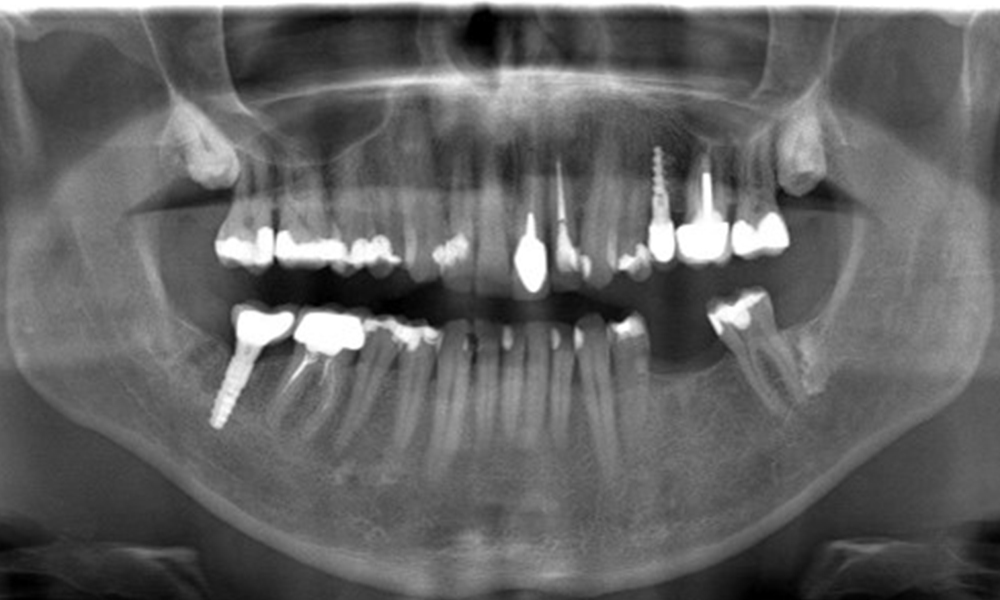

In the medical history, the 55-year-old patient states that he has no systemic disease and is not taking any medication. The patient’s lifestyle is similarly unremarkable. The patient has a few tooth restorations and two implants (2nd and 4th quadrants). On the basis of current findings, gingivitis is identified in an otherwise stable periodontal condition on the reduced periodontium (stage III, grade A).

Previous treatments: dental restorations (non-precious metal/ceramic blend), two implants (2nd, 4th quadrants)

The X-ray image shows the bone loss

The X-ray images show the bone loss.

OPG: 29/02/2024

X-ray images (or bitewing X-rays)